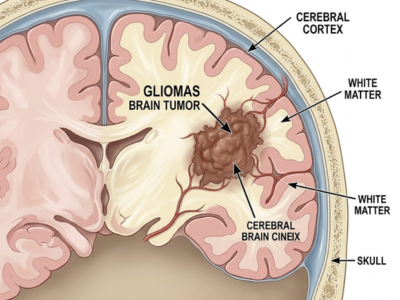

Gliomas

Tumors originating in the supportive glial cells of the brain.